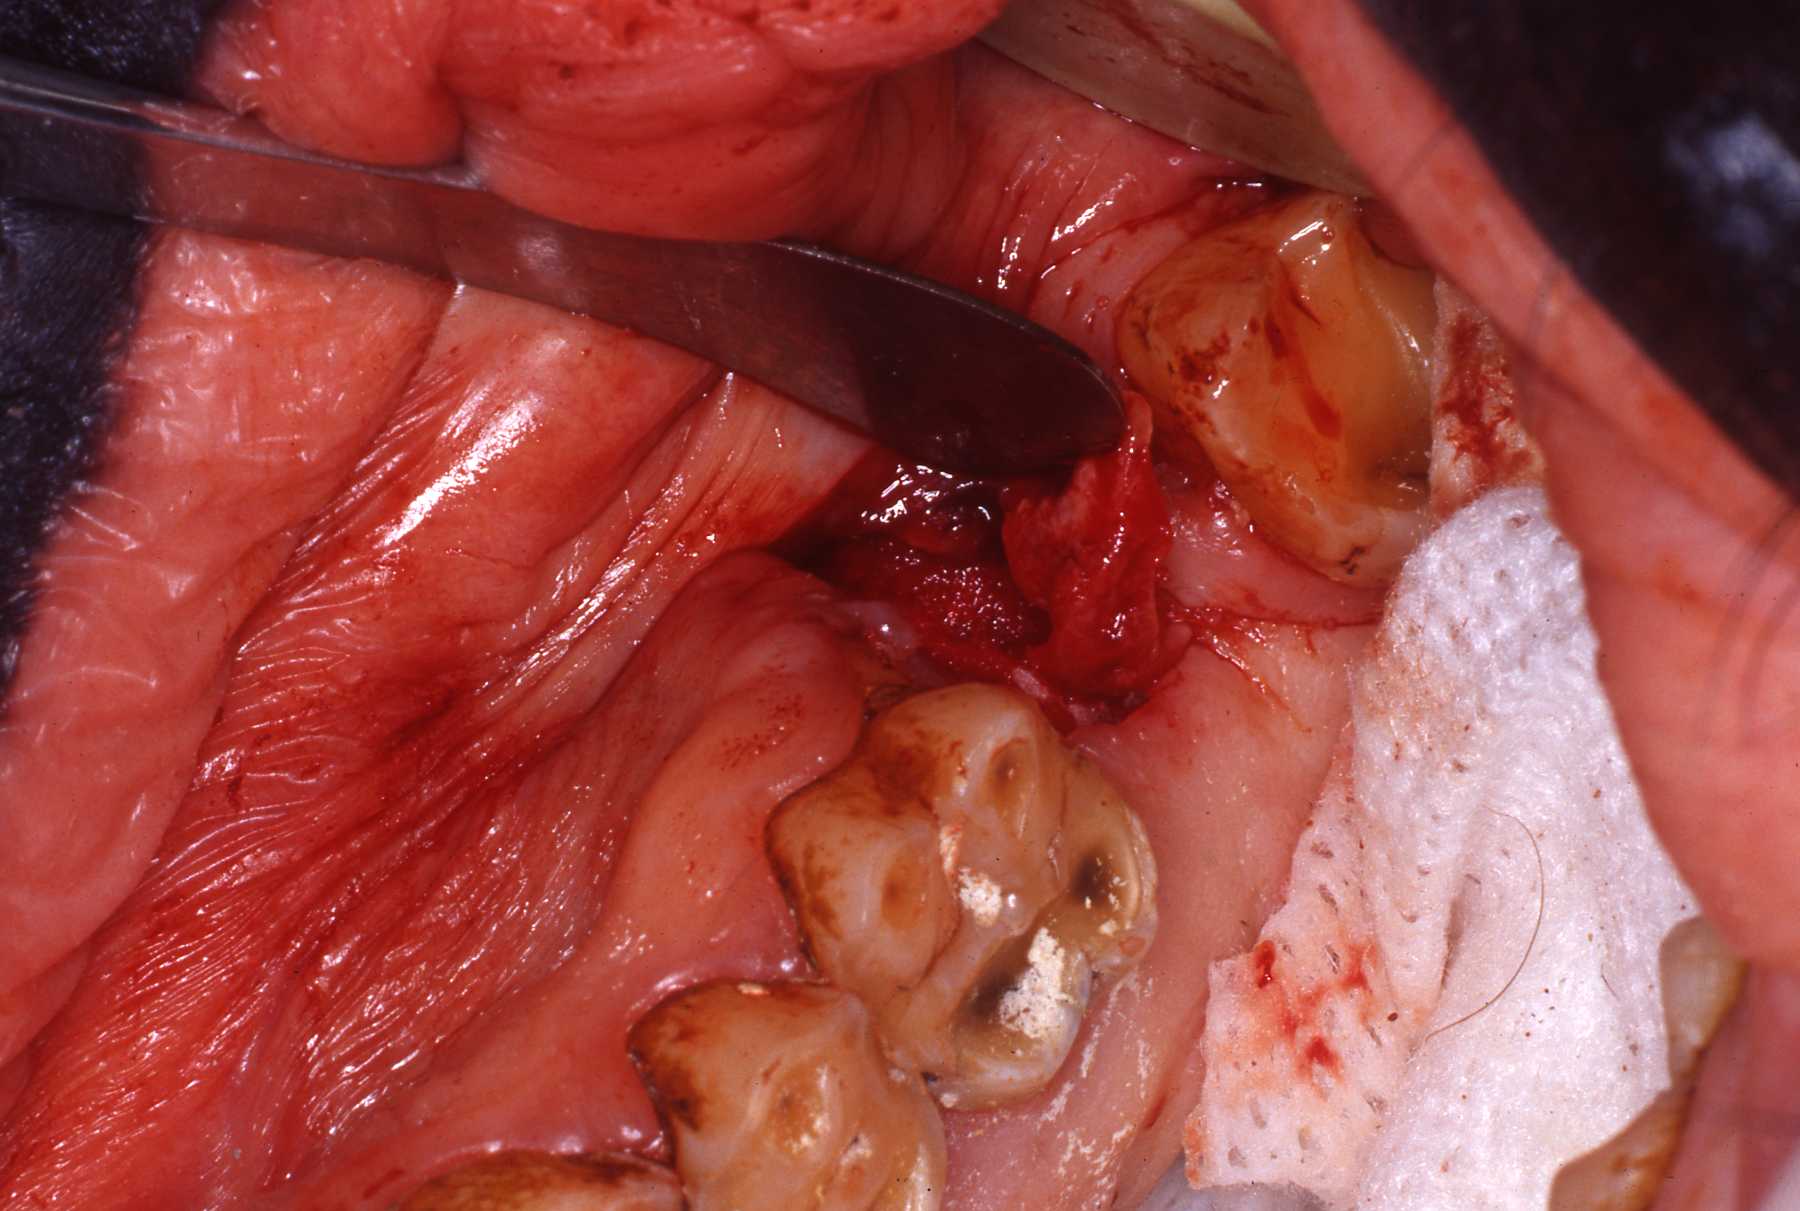

Fistula explored

Fistula exposed

Fistula being repaired

Fistula exposed, tensionless flap